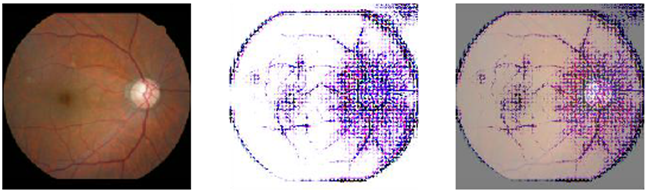

닥터눈 CVD는 인공지능을 활용하여 망막 이미지를 분석합니다. 환자는 양쪽 눈의 망막을 촬영한 후, AI가 자동으로 분석하여 심혈관 위험 평가 결과를 3분 내에 제공합니다. 이 과정은 매우 간단하며, 환자에게 큰 부담을 주지 않습니다.

와 같은 망막 이미지를 통해 혈관의 상태를 확인하고, 이를 바탕으로 심혈관질환의 위험도를 평가합니다. 메디웨일의 '닥터눈 CVD'는 눈 검사만으로 심혈관 질환 위험을 예측하는 인공지능(AI) 기반 설루션으로, 최근 국회 포럼에서 선보여 큰 주목을 받았습니다. 주요 내용은 다음과 같습니다.

눈 검사를 통해 심혈관질환의 위험을 예측하는 방법은 여러 가지가 있습니다. 예를 들어, 망막의 혈관 구조를 분석하여 혈관의 두께, 분포, 그리고 이상 유무를 확인합니다. 이러한 정보는 심혈관질환의 발생 가능성을 예측하는 데 중요한 역할을 합니다.

와 같은 다양한 망막 이미지를 통해 혈관의 상태를 비교하고, 이를 바탕으로 위험도를 평가할 수 있습니다.

에서 볼 수 있듯이, 눈의 혈관 상태를 분석하는 과정은 AI의 도움으로 더욱 정교해지고 있습니다.